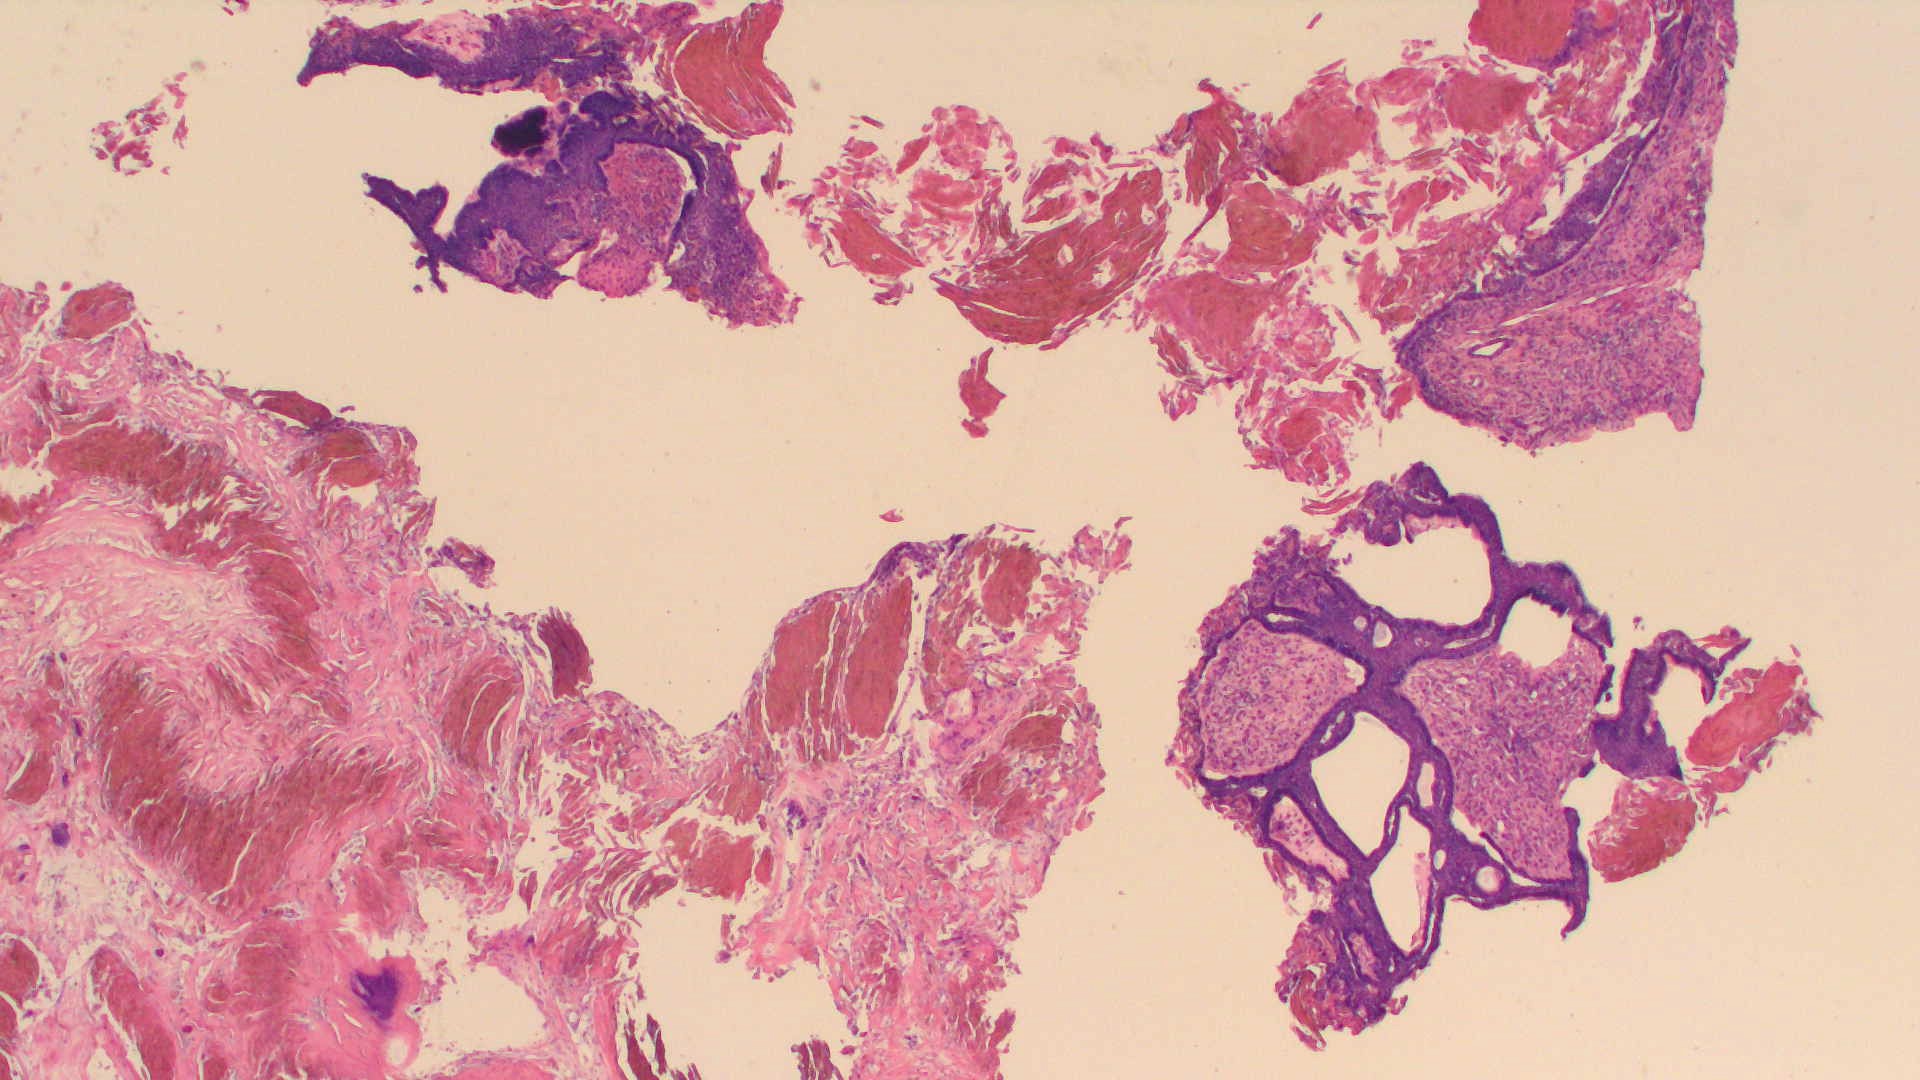

Dx: Adamantinomatous craniopharyngioma, WHO Grade 1

-3 micro features – wet keratin, basal palisading and loose reticulum